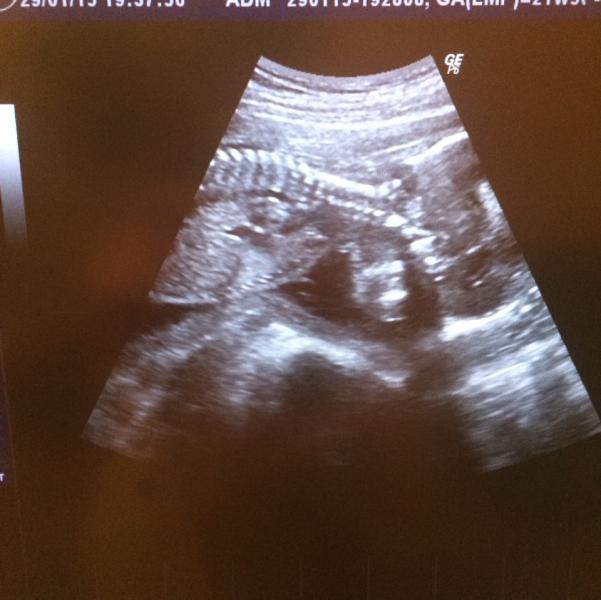

Этой новостью я еще не остыла, поэтому решила посвятить пост #2 полу нашего малыша👼. Это была ооочень долгожданная новость, узнали мы несколько дней назад, аж на 22 неделе, когда все мои знакомые беременные уже знали кто у них будет 😼 Так вот - мы ждем мальчика! 👶 честно говоря, это было так же неожиданно, как и вся наша беременность 😸🙀 потому что я интуитивно думала что будет девочка (хотя всегда хотела сына), муж хотел девочку и мои родители тоже. Одна свекровь сорвала джекпот 😏👵 Теперь у на...